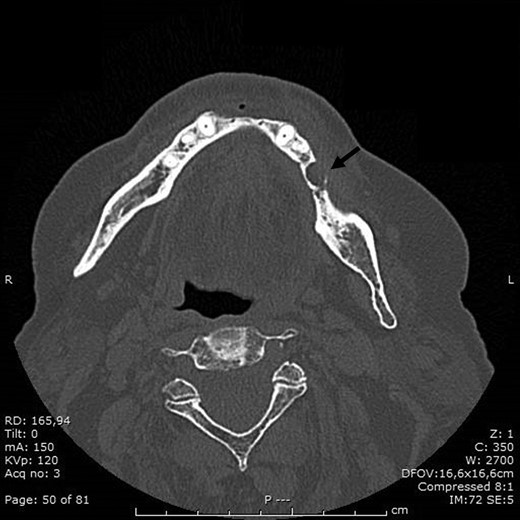

BRONJ had been clinically diagnosed at the patient’s first visit and confirmed radiologically by the dental x-ray and CT performed in September 2016, which showed marked demineralization of the anterior portion of the orbital ethmoid wall on the right, left mandibular osteonecrosis in the premolar region, a small periapical granuloma in position 44 and diffuse upper and lower alveolar atrophy.

In view of the intraoral clinical picture and, in particular, of the incapacitating pain, it was decided that the patient should undergo surgery with mandibular bone curettage and positioning of HAM (Fig. 1).

In November 2016 the patient underwent surgery under general anaesthesia (same technique used for the first patient described) (Fig. 4A–D). The mesial and distal bone curettage margins were dictated by the x-ray images (Fig. 5) which identified above all the radio-opaque areas, often associated with a periosteal reaction, as well as by the need to remove any bone sequestra present. The HAM was 3 × 3 cm2 in size and was positioned over the curetted area and under the mucosal flap.